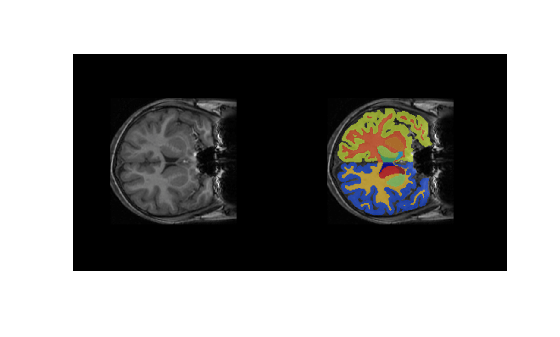

cropIdx,metaData,classNames,labelIDs);Overlay a slice from the predicted segmentation map on a corresponding slice from the input volume using the labeloverlay function. Include all the brain structure labels except the background label. Because the labeloverlay function is not supported on GPU, transfer the test slice from GPU memory to host memory before calling labeloverlay.

sliceIdx = 80;

testSlice = rescale(vol(:,:,sliceIdx));

testSlice = gather(testSlice);

predSegMap = predictedSegMaps(:,:,sliceIdx);

B = labeloverlay(testSlice,predSegMap,IncludedLabels=2:32);

figure

montage({testSlice,B})